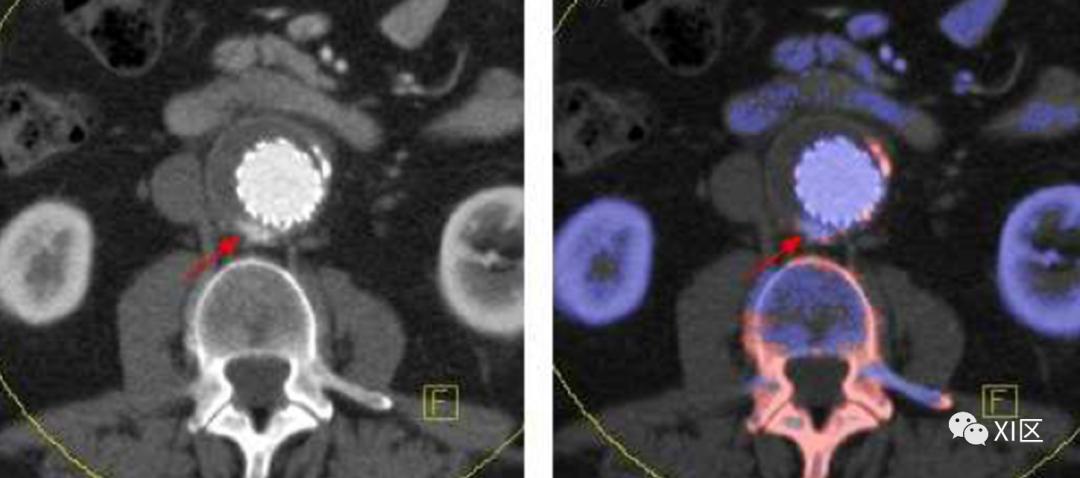

有效原子序数(Zeff)表示化合物或材料混合物的平均原子序数。另一方面,密度代表电子在另一个位置的概率。通过基于原始数据的双能分析计算出了高度精确的电子密度和有效原子序数,但其临床适用性需要进一步研究。

图21 60岁男子出现急性腹痛。腹部增强检查的后处理Rho/Z图清楚地显示了埋伏的异位胆囊结石(B 黑色箭头)。在70keV的图像上看不到胆结石,因为它与回肠远端周围液体的衰减相似(A)。基于双能CT的电子密度成像引起了放射肿瘤学家的兴趣。在放疗计划期间,传统CT扫描生成电子密度图,以确定靶组织中的剂量分布。然而,由于CT值不仅取决于电子密度,而且还取决于有效原子序数,因此CT值与组织的电子密度没有精确的相关性。据报道,双能量CT扫描获得的电子密度图比常规放疗计划方法获得的电子密度图更精确。